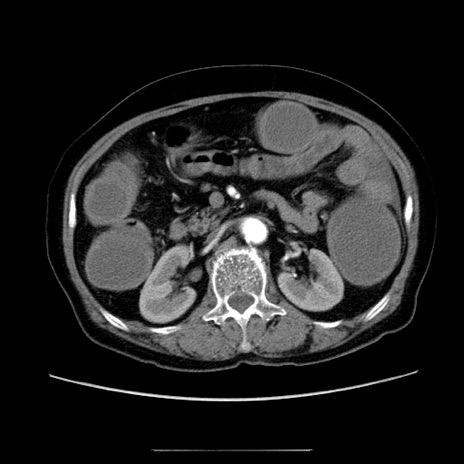

【症例】70歳代女性

【主訴】お腹が張る

【現病歴】1週間くらい前から腹部膨満の自覚あり。昨日夜から増悪したため、本日救急外来受診。

【身体所見】意識清明、BT 36.5℃、BP 165/106mmHg、HR 80bpm、SpO2 98%、腹部:膨満、軟、自発痛・圧痛なし、触診にて不快感あり、腸蠕動音:減弱

【データ】WBC 12600、CRP 1.04